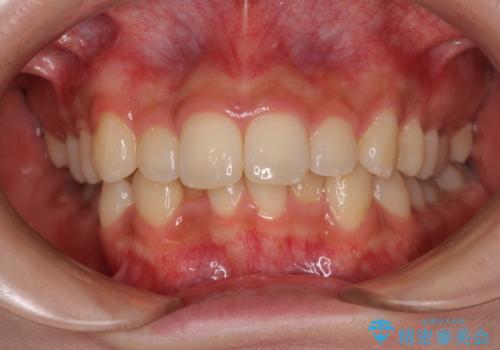

- 抜歯をせず前歯の角度を改善するマウスピース矯正治療

- 奥歯の咬み合わせのズレと前歯の突出感 変則的な抜歯矯正

- 前歯を後ろに下げたい ワイヤー矯正(クリア装置)

- 突き出た前歯を治したい 小臼歯抜歯+マルチブラケット矯正- 担当医 大元洋佑